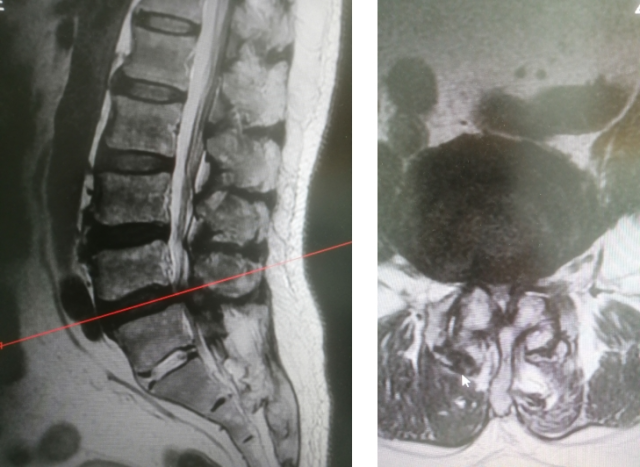

72岁的张大伯腰部牵拉下肢疼痛反反复复十余年,严重时无法走路,曾数次住院,口服药物、各种理疗等保守治疗无法明显缓解,疼痛让张大伯寝食不安,精神状态极差。在家人陪同下来到疼痛科住院治疗,在经过腰椎CT检查后,诊断为腰椎间盘突出,椎管狭窄。

张大伯的腰椎间盘MRI。

考虑患者保守治疗欠佳,也不愿行椎管减压手术,为缓解患者疼痛,疼痛科温力生主任为患者进行“脉冲射频+神经阻滞术”,使用CT精准定位椎间孔区域,将射频针穿刺至神经根处,经过感觉测试、运动测试后确认疼痛位置,连接电极片及电极线,通过数分钟脉冲射频治疗阻断神经疼痛信号,达到治疗目的。术后患者腰部及下肢牵拉痛、活动受限得到明显缓解,第二天可下床走路,手术创伤口几乎看不见;张大伯当即开心笑起来,吃饭好了、睡觉也舒服了,也能走路了,对治疗效果非常满意。